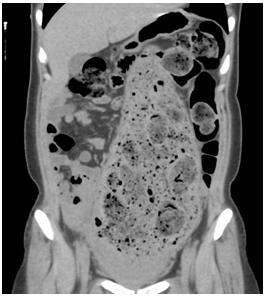

一個(gè)月前剛剛生產(chǎn),與生產(chǎn)部位完全吻合的巨大糞便塊。馬上進(jìn)行了腹部CT 檢查。

照片6:腹部CT

乙狀結(jié)腸出現(xiàn)明顯擴(kuò)張,2周的糞便鑲嵌其中。乙狀結(jié)腸上部將肝下方,胃和橫結(jié)腸向上方擠壓,左側(cè)乙狀結(jié)腸下方可確認(rèn)內(nèi)腔積蓄圓形糞便和氣體。

通常,結(jié)腸直徑超過(guò)10cm后壓力差可能穿破腸壁。本病例中,結(jié)腸已經(jīng)超負(fù)荷擴(kuò)張。實(shí)際上,患者的腸道長(zhǎng)時(shí)間擴(kuò)張,因沒(méi)有基礎(chǔ)疾病,被診斷為慢性假性腸閉塞癥。可能導(dǎo)致腸道腸肌神經(jīng)叢或粘膜下神經(jīng)叢的功能障礙。